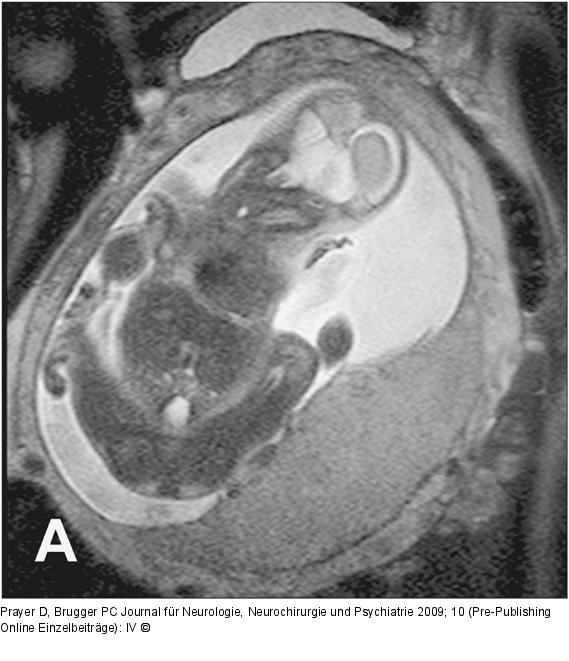

Abbildung 6a-b: Plazenta - 26. SSW A. Normale, homogene und glatt begrenzte Plazenta in der 26. SSW. B. Gleiche SSW, die Plazenta hat jedoch eine pathologisch unruhige Binnenstruktur und eine unregelmäßige Oberfläche. Der Fetus weist eine Wachstumsrestriktion auf. |

A. Normale, homogene und glatt begrenzte Plazenta in der 26. SSW. B. Gleiche SSW, die Plazenta hat jedoch eine pathologisch unruhige Binnenstruktur und eine unregelmäßige Oberfläche. Der Fetus weist eine Wachstumsrestriktion auf. |